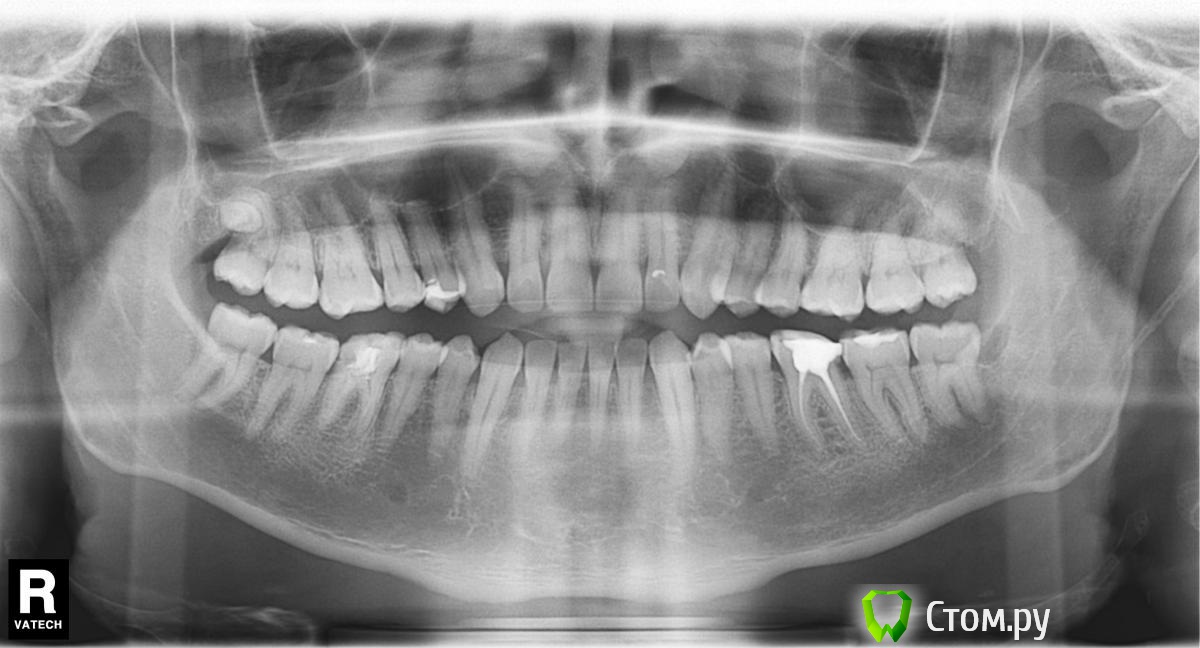

Leonid__ Опубликовано 25 января, 2014 Поделиться Опубликовано 25 января, 2014 Здравствуйте.Нуждаюсь в совете. Опухла десна слева рядом с зубом мудрости. Крайне больно жевать, глотать и открывать широко рот. Лимфоузлы с этой стороны воспалены, на ощупь болезненные. Кажется есть температура. Функционирую на обезболивающих.Я нахожусь в Таиланде. Был сегодня у врача. Он, взглянув на десну, почти сразу предложил мне удалить зуб мудрости. Я для порядка решил сделать снимок. Собственно, вопрос - удалять или не удалять? Что делать с воспалением? (Про антибиотики врач ничего не сказал) Ссылка на комментарий